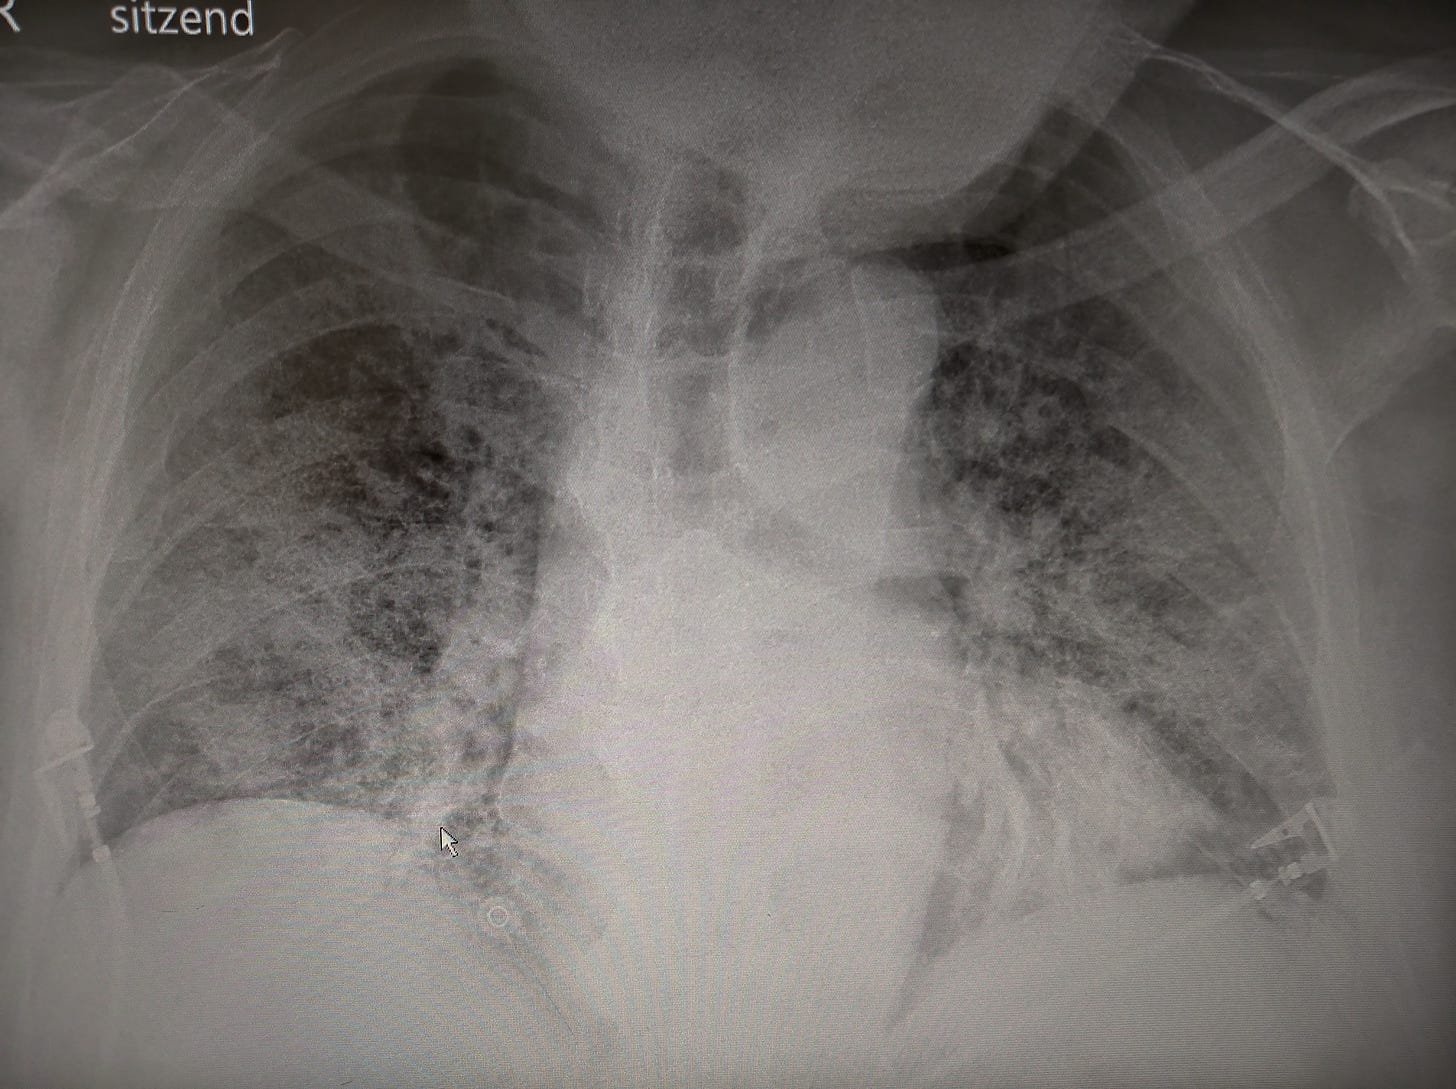

Wobei „behandeln“ ein Euphemismus ist. Viel mehr als Sauerstoff, Fiebersenkung, Zuspruch und das rechtzeitige Erkennen der Intensivpflicht konnten wir anfangs nicht bieten. Die ersten Patienten erhielten zudem Hydroxychloroquin, weil es vage Hinweise aus Laborversuchen gab, dass dieses eigentlich zur Behandlung der Malaria und einiger Autoimmunerkrankungen verwendete Medikament auch gegen dieses SARS-CoV-2 wirken würde. Das stellte sich später als falsch heraus, weshalb die Verwendung bald gestoppt wurde. Das beeindruckte manche Verharmloser nicht. Sie verwendeten Hydroxychloroquin wie später auch das Wurmmittel Ivermectin.

Der 55-jährige Arbeiter, der im März 2020 als einer der Ersten auf unsere Intensivstation kam. Direkt von der Baustelle, mit Fieber und Atemnot. Typ serbischer Bär, ein Leben am Bau. Er musste rasch intubiert werden, eine Woche später war der Bär tot. #YesWeCare

Die 65-Jährige, die zwei Wochen intubiert auf der Intensiv lag. Als sich die Lunge wieder besserte, die Beatmung und damit auch die Medikamente reduziert werden konnten, wachte sie nicht auf. Die Computertomografie des Kopfes zeigte, dass ihr Gehirn mit zahlreichen kleinen Insultarealen durchsetzt war. Sie wachte nie mehr auf. #YesWeCare

Der 65-Jährige, der mit einer Sauerstoffsättigung von 50% immer noch stand. Extremes Beispiel der sogenannten „happy hypoxemia“. Vor allem aber die Verzweiflung des Sanitäters, der in der dritten COVID-Welle versuchte, für ihn ein Bett mitten in der zusammenbrechenden Versorgung zu bekommen.

Der 80-Jährige mit Myasthenia gravis und COVID-Pneumonie. Die diensthabende Oberärztin der Notfall holte mich, um eine Übernahme auf die ICU zu besprechen. Der 80-Jährige schaute mich lächelnd und schnaufend an, ich lehnte die Übernahme ab, die Kollegin weinte. Ich: „Du weißt doch, er hat keine Chance.“ Sie: „Ja, natürlich, aber ich pack's trotzdem nicht.“ #YesWeCare